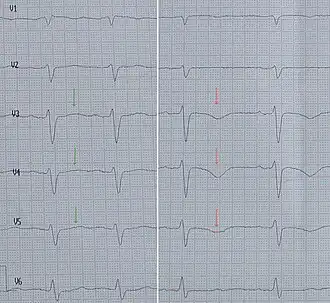

EKG

Das EKG zeigt in der Akutphase Hebungen der ST-Strecke (vgl. EKG-Nomenklatur) oder diffuse Veränderungen der T-Welle, innerhalb der ersten 48 Stunden oft auch eine Verlängerung der QT-Zeit. Die EKG-Veränderungen sind jenen bei einem Herzinfarkt ähnlich und treten häufig in mehreren EKG-Ableitungen auf.[7][22]